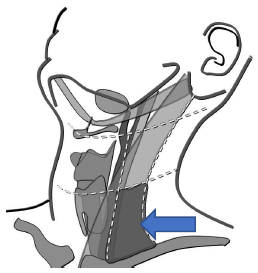

Qual o nível cervical destacado?